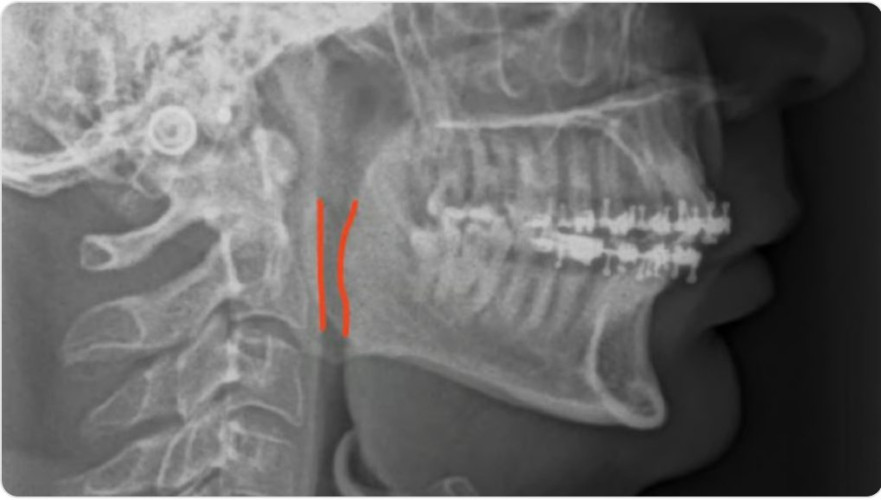

وتابع: بعد إجراء الفحوصات والاستشارات اللازمة من جراحة الوجه والفكين، وإجراء الأشعة المقطعية المطلوبة، وعمل التخطيط الجراحي ثلاثي الأبعاد، تم تشخيصه بعدم تطابق هيكلي من الصنف الثاني، وضيق بالمساحة الخلفية للمجرى الهوائي، والذي يبلغ لدى المريض 8 مم، في حين تبلغ المساحة الطبيعية أكثر من 10 مم.

وأشار إلى أن العملية التي تضمنت تصحيح التطابق الهيكلي، أجريت بتقديم الفكين العلوي والسفلي، بالإضافة إلى تقديم الذقن، ونجحت العملية بالعلاج وظيفيًّا بزيادة حجم المساحة الخلفية للمجرى الهوائي، أدّت لعدم استخدامه لأي جهاز عند النوم، ونجحت العملية كذلك بالعلاج جماليًّا بتحسين العلاقة الوجهية والتناسق الهيكلي.